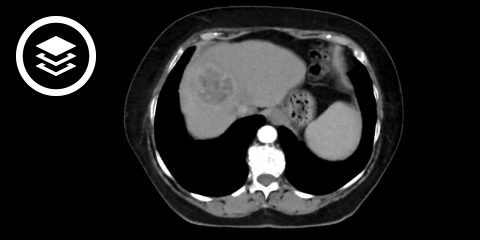

CT-Fallbeispiel

DICOM-Modelle können auf Mobilgeräten leider nicht angezeigt werden.

In der Sonographie kann eine solide Raumforderung abgegrenzt werden. Mittels kontrastmittelgestützter Sonographie (CEUS), Computertomographie (CT) und/oder Magnetresonanztomographie (MRT) erfolgt eine relativ genaue Abgrenzung und Zuordnung des Tumors. Charakteristisch für das HCC ist eine Kontrastmittelanreicherung (Hyperperfusion) in der arteriellen Phase mit nachfolgend raschem wash-out in der portalvenösen und venösen Phase. Ein weiteres Kriterium ist eine Größe der Raumforderung von > 1 cm. Die Befunde der Bildgebung werden bei Risikopatienten mit Hilfe des Liver Imaging Reporting and Data Systems (LI-RADS®) klassifiziert.[3] Insbesondere bei kleineren Läsionen weist die MRT eine höhere Sensitivität als die CT auf, daher sollte in erster Linie eine MRT erfolgen. Falls der Befund unklar bleibt oder Kontraindikationen für eine MRT bestehen, ist eine triphasische CT oder eine CEUS anzuschließen.

- Bildquelle DICOM-Viewer: Datensatz freundlicherweise zur Verfügung gestellt durch die Klinik für diagnostische und interventionelle Radiologie, St. Vinzenz Hospital Köln